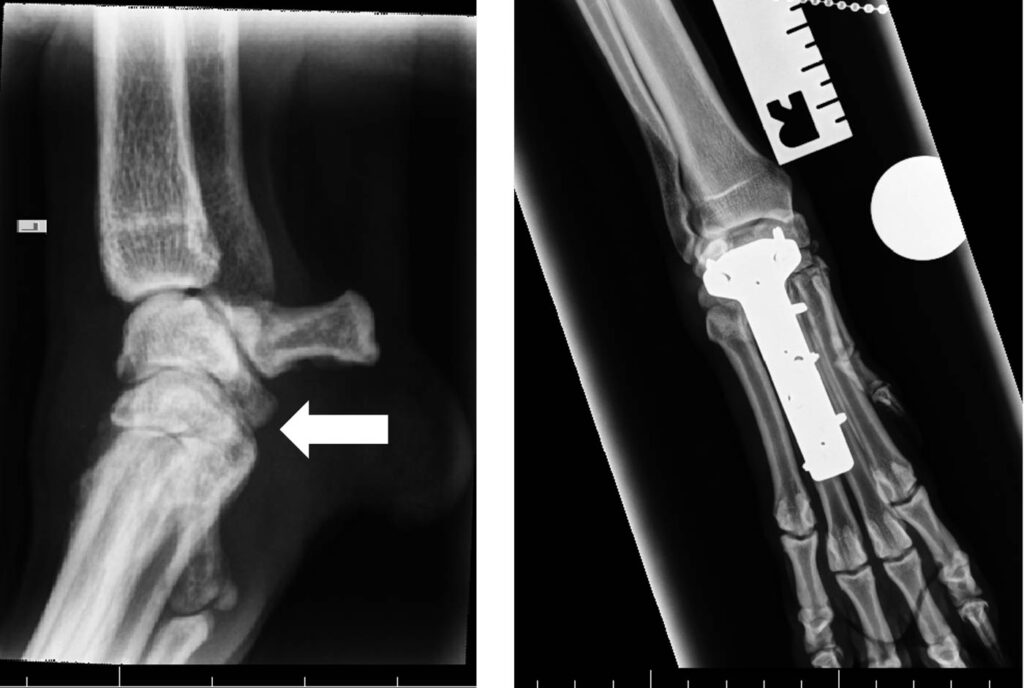

Injury or degeration of the palmar ligament can cause the carpus to ‘sink’. Failure of the palmar ligament can occur at one or more levels and it is important to assess the injury carefully. Splinting or casting of such injuries is destined to fail and surgery is receommended. However, careful assessment of the injury is required because if the antebrachiocarpal joint is unaffected, and can be saved, this has important long-term consequences for the dog. If this is the case, partial carpal arthrodesis can be performed using specially designed plates and bone graft.

If the antebrachiocarpal joint is affected, full fusion (pancarpal) arthrodesis can be performed and will restore function in the short-medium term although arthritis of neighbouring joints is likely in the long term. Careful assessment of these injuries with a specialist is recommended so that clients can make infiormed decisions for their pet.